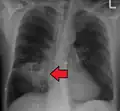

Pulmonary abscess on CXR -